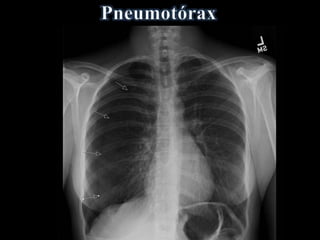

• Ar livre na cavidade pleural

• Faixa de ar (hiperlúcida) entre a pleura

visceral e:

a parede torácica e/ou diafragma

• Desvio de mediastino contralateralmente

• Acentuado na Expiração Forçada